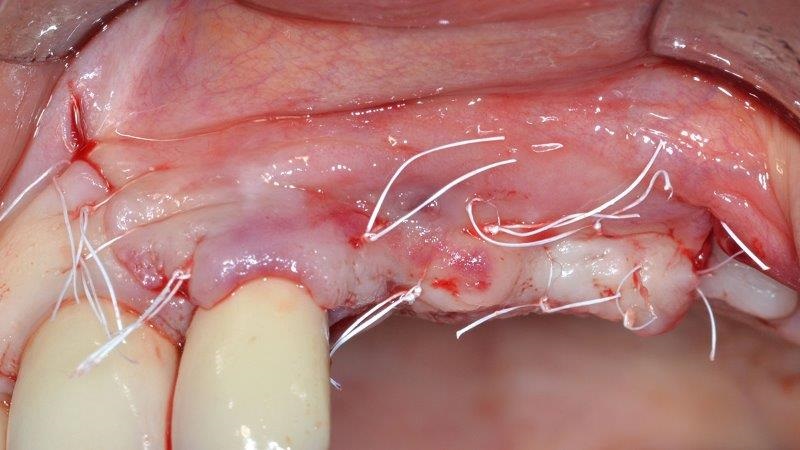

Alloplastic biomaterial (Activioss) was grafted into the defect to support the membrane and promote blood clot stabilization (Fig. 13); the membrane was folded on the graft, then stabilized with Ustomed titanium pins (Fig. 14). A tension-free flap closure was achieved, then sutured using 5-0 nonresorbable PTFE sutures (Fig. 15).

To increase the keratinized tissue width, the flap was apically positioned and sutured with crossed horizontal mattress sutures (Fig. 20). Sutures were removed after seven days and the patient was sent back to the referring dentist. Supragingival professional tooth cleaning was performed every week for 60 days and the patient was followed up with every three months until healing had occurred with no complications or adverse events.